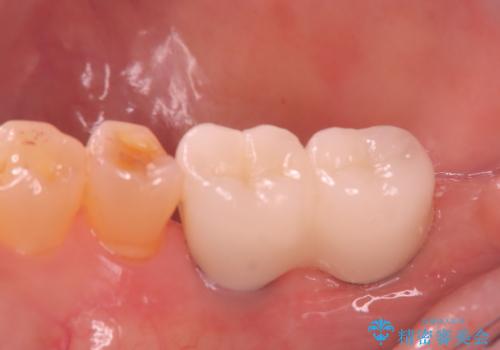

大きなむし歯と欠損をセラミックに 部分矯正を併用した総合歯科治療